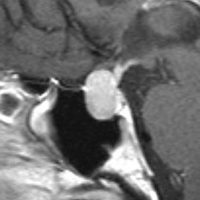

左は下垂体腺腫(緑の腫瘍)が内頚動脈に挟まれていることを示しています。

中央は手術前の下垂体腺腫で,視神経も正常下垂体も位置はわかりません。

右は手術翌日の画像です。黄色の矢印の先が残した正常下垂体組織です。桃色の矢印の先に視神経(視交叉)がはっきり見えています。術後の一時的な尿崩症がありました。クモ膜が残っているので髄液漏は生じませんでした。でも正常下垂体組織(黄色矢印)も視交叉も腫瘍に圧迫されてペラペラになっていますから,いつもうまく行くとは限りません。